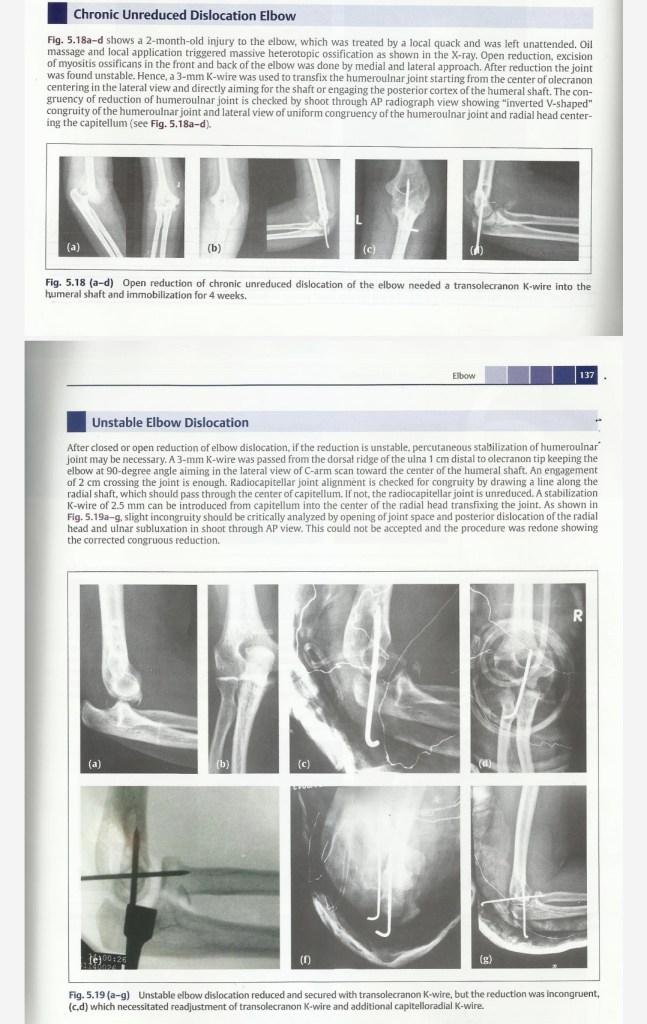

Lecture Elbow dislocation